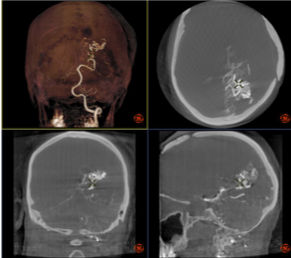

As an interventionalist, you want to diagnose and treat all your patients, even the most challenging ones, safely and efficiently, with the best possible image quality. Designed for cardiac and peripheral procedures, the OptimaTMIGS 330 is based on proven technology and very efficient imaging chain, providing superior image quality at lowest possible dose.

It includes features like Dose Personalization, which gives you the tools to choose from up to four automatic exposure preferences for your system. You can also modify any of these preferences1in any clinical protocol to enable multi-procedure, m ulti-user customization and thus support well-informed decisions.Powered with a comprehensive set of advanced interventional imaging software, you can expand your clinical versatility and successfully plan, guide and assess increasingly sophisticated procedures with greater precision and dose efficiency.